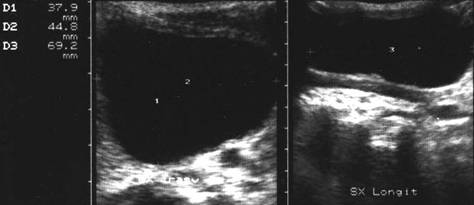

Femeie de 74 ani. Carcinom anaplazic voluminos in lobul

drept.

La examenul eco cu sonda convexa de 5.0 MHz leziunea pare benigna